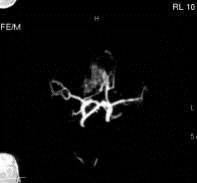

问题 病历摘要:??患者男性,56岁,因右侧视力下降伴视野缺损2个月来院就诊,诉头痛,无明显头晕,无视物重影,无恶心呕吐,无肢体抽搐,无肢体乏力,胃纳佳,大小便正常,既往史无特殊,入院检查:神志清楚,言语清楚,体毛分布正常,左侧视力4.6,右侧视力4.0,粗侧右颞侧视野缺损,左侧正常,颈软,四肢肌张力正常,肌力正常,病理征(-)。 在巨型动脉瘤手术中,若术中需要夹闭载瘤动脉,下述那些方法可先预测夹闭后的效果可能是好的?提示:本例病患采用开颅手术治疗

选项 A.Matas试验阴性 B.压迫患者颈动脉,健侧颈动脉造影,患侧大脑中动脉、前动脉不显影 C.压迫患者颈动脉,行椎动脉造影,患侧颈内动脉、大脑中动脉、前动脉显影 D.压迫患者颈动脉,行椎动脉造影,患侧颈内动脉不显影 E.经颅超声监护,临时夹闭颈动脉,大脑中动脉血流速度保持16cm/s以上 F.脑电图监护,临时夹闭颈动脉,脑电图提示慢波增多不显著